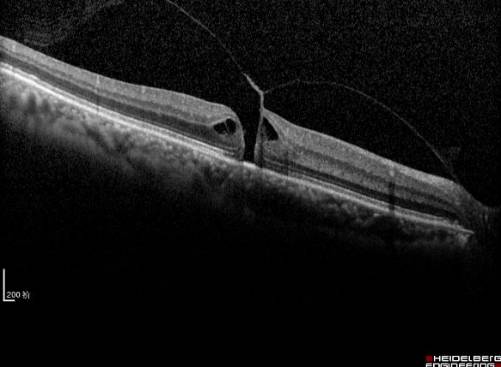

黄斑疾病多由先天发育异常或后天病损引起,临床上后者占绝大多数。一般来说,黄斑疾病多见于老年人,但目前黄斑疾病有低龄化和高发病的趋势。由于检查技术的日益精准,以往无法解释的视力问题越来越多的发现是由于黄斑部的细微病变造成的。常见的黄斑疾病包括年龄相关性黄斑变性(见图1)、特发性息肉状脉络膜血管病变、玻璃体黄斑牵拉综合征、黄斑前膜(见图2)、黄斑裂孔、高度近视黄斑病变(见图3)和中心性浆液性脉络膜视网膜病变等。

图1. 年龄相关性黄斑变性